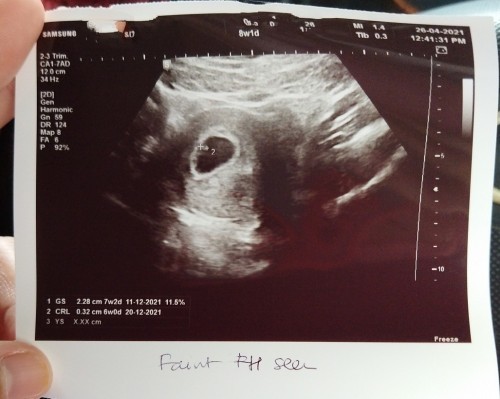

scan 8weeks

salam momies, tdi sy scan kandungan 8weeks 1day, doc ckpp baby kecil sngat, mcm bkn pregnant 8weeks, d sbb masa bujang period tak teratur, ada tak yg pernah mcm ni? baby ok ja kan? sy risau jer, nak minta pendapat momies sekalian

sy scan 8w , bby masi kcik . dgr heartbeat & nmpk kantung jk . insya allah bby kmu ok . yg pntg dgr bnyi heartbeat bby.